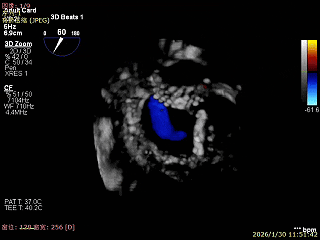

3D Enface 2区及3区前叶脱向左房

3D Enface 可见反流由2区3区从前后冲出